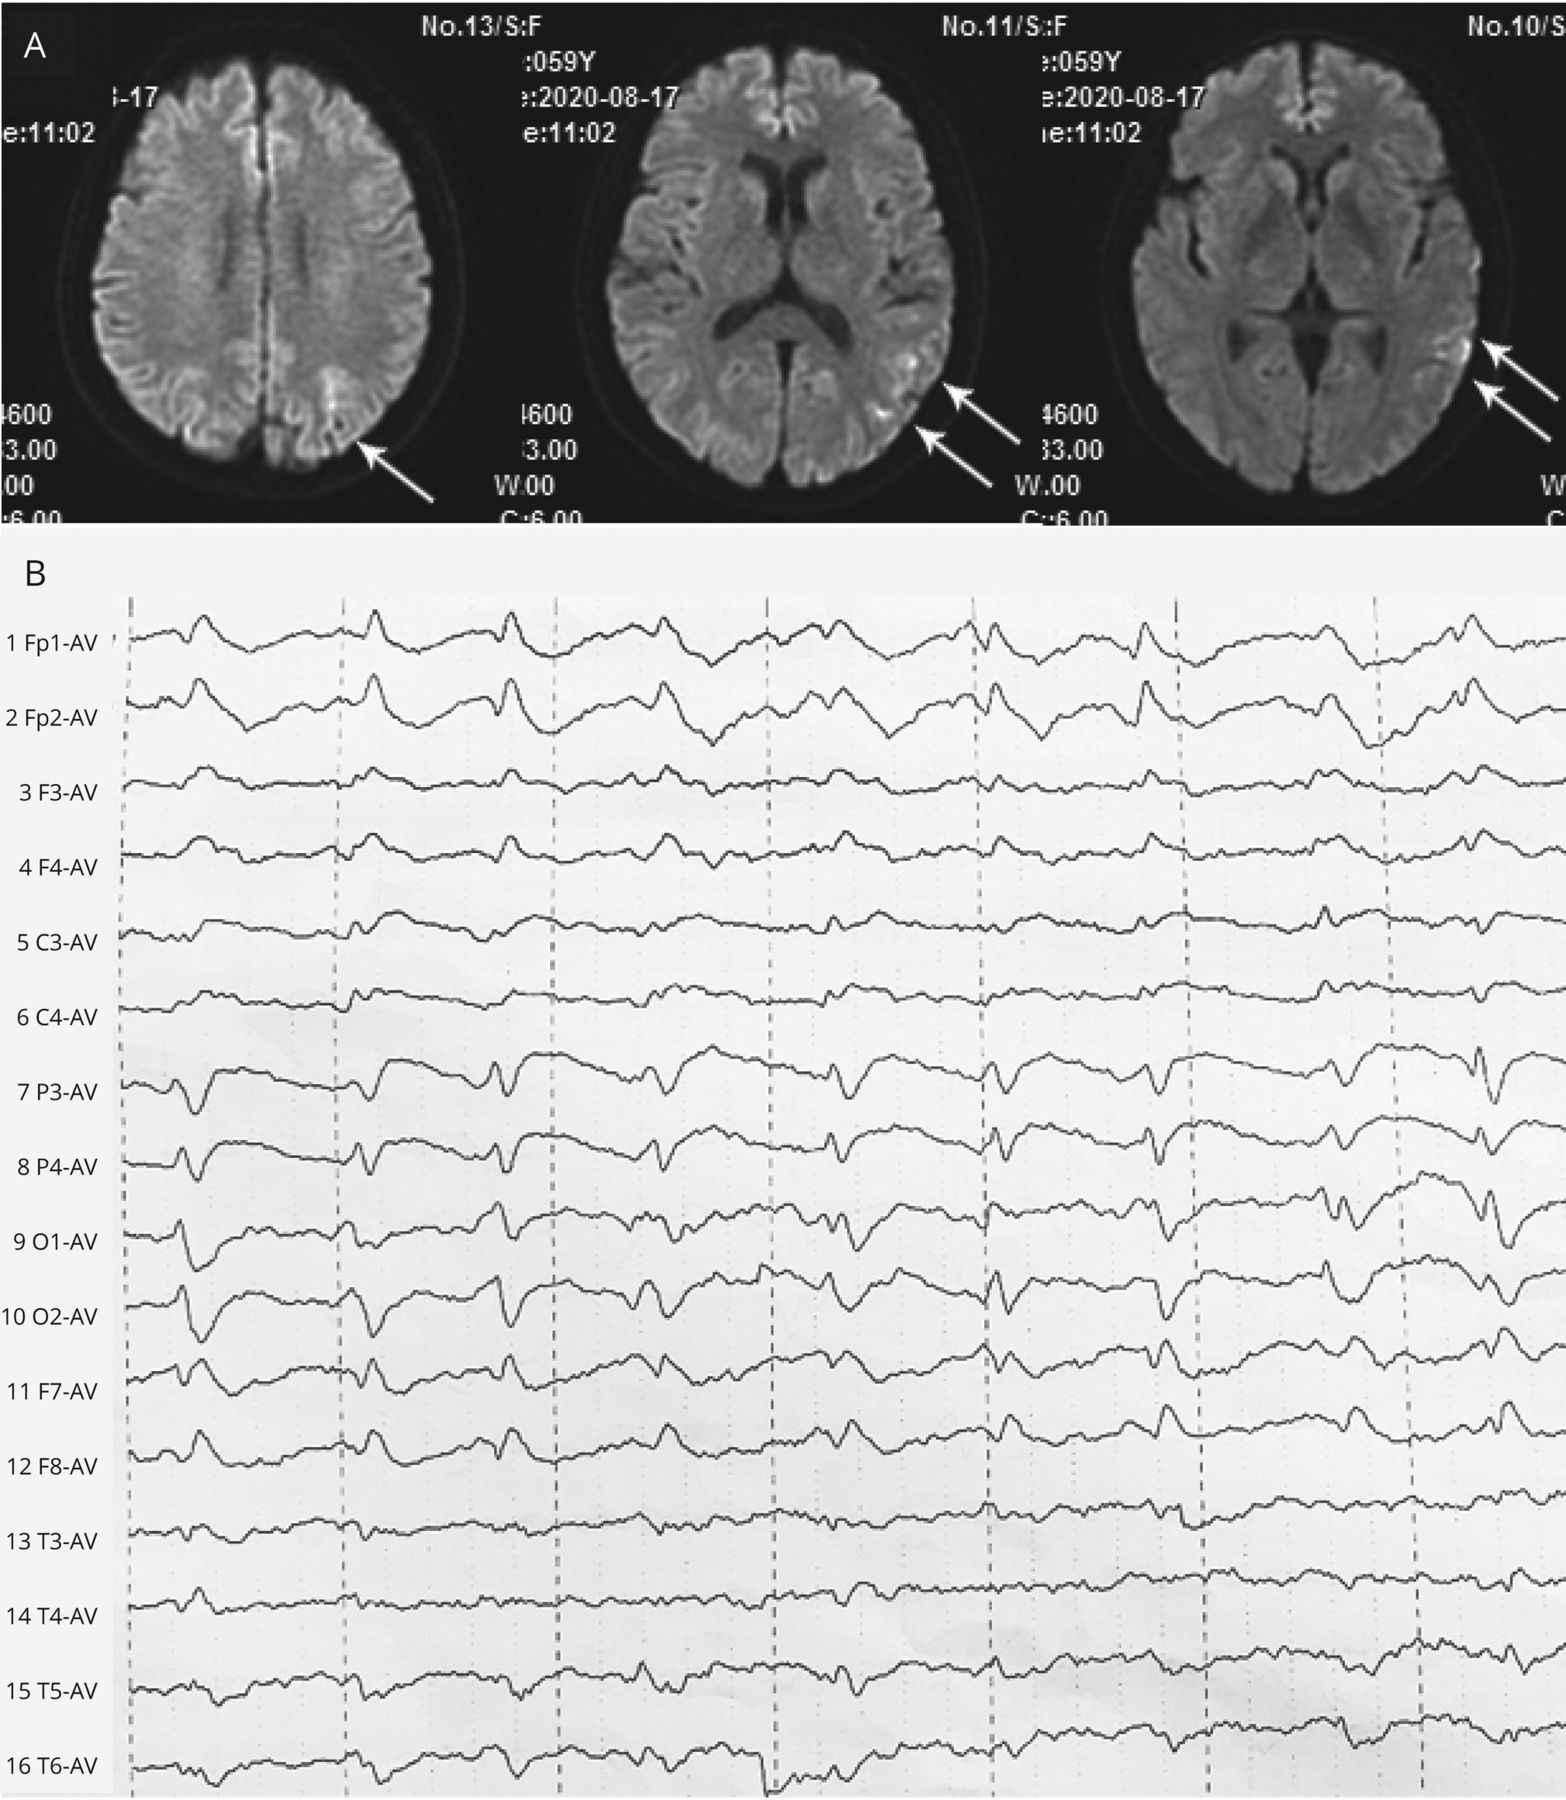

59岁的女人面对亚急性发作的手笨拙失忆紧随其后。她伸手报道困难对象,虽然她可以看到他们。考试(视频1)显示视神经共济失调,或者20/30的视力,完整的视野,和正常的finger-to-nose测试。Hyperintense diffusion-weighted MRI信号在左temporo-parieto-occipital皮层,周期性三相的复合物在脑电图(图),高架t-tau CSF建议Heidenhain变异克雅氏病的疾病。1病人接受支持性护理,发展到无着丝粒的缄默症。视神经视觉引导的手臂动作ataxia-inaccuracy visuomotor障碍与涉及后顶叶皮层的损伤有关。2

图

Diffusion-Weighted MRI和脑电图

(一)Diffusion-weighted MRI显示hyperintense信号(箭头)在左temporo-parieto-occipital皮层。(B)脑电图显示周期在1 / s三相的复合物。